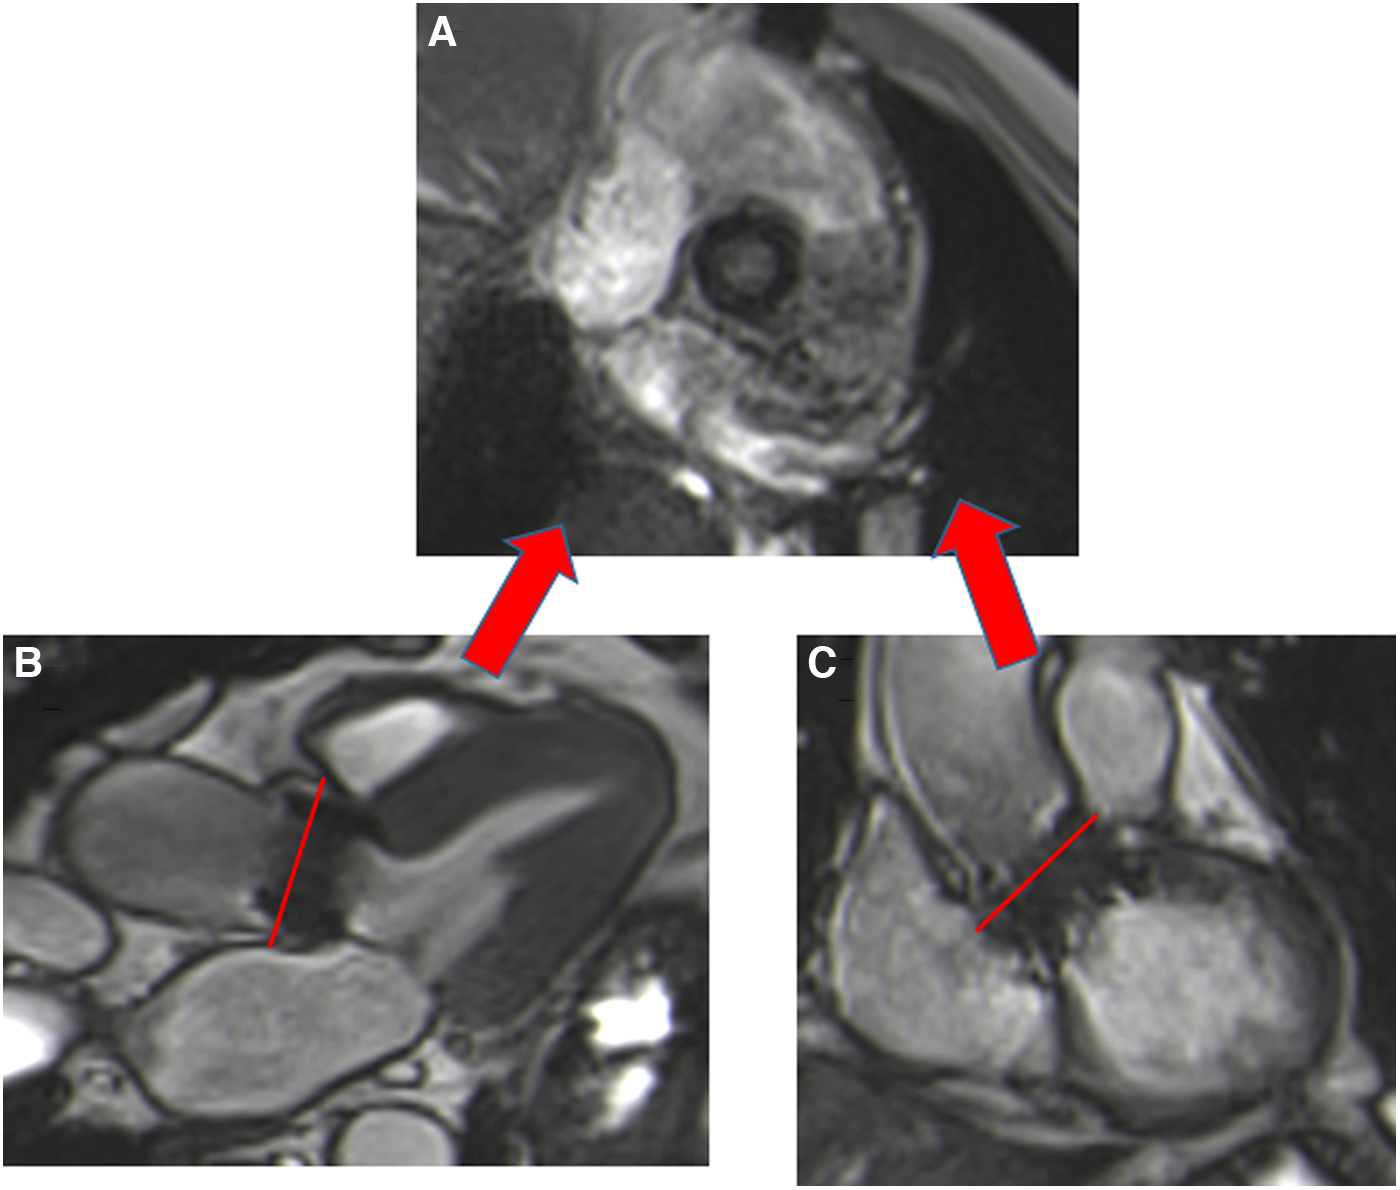

Susceptibility to artefacts can be extensive for patients with TAVI, despite the absence of sternal wire artefacts, especially for the Corevalve® prosthesis due to a large stent from the LVOT beyond the sinotubular junction, making measurement of the orifice area unfeasible. Aortic orifice planimetry can also be challenging for the Edwards-Sapien® prosthesis (Figure 5).

Figure 5

Visualization of the orifice of the Edwards-Sapien prosthesis (A) obtained from two orthogonal planes: three-chamber view (B) and coronal LVOT (C). CMR stent-related artefacts prevent accurate aortic valve planimetry.